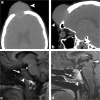

Calvarial lesions are often asymptomatic and are usually discovered incidentally during computed tomography or magnetic resonance imaging of the brain. Calvarial lesions can be benign or malignant. Although the majority of skull lesions are benign, it is important to be familiar with their imaging characteristics and to recognise those with malignant features where more aggressive management is needed. Clinical information such as the age of the patient, as well as the patient's history is fundamental in making the correct diagnosis. In this article, we will review the imaging features of both common and uncommon calvarial lesions, as well as mimics of these lesions found in clinical practice. TEACHING POINTS: • Skull lesions are usually discovered incidentally; they can be benign or malignant. • Metastases are the most frequent cause of skull lesions. • Metastatic lesions are most commonly due to breast cancer in adults and neuroblastoma in children. • Multiple myeloma presents as the classic "punched out" lytic lesions on radiographs. • Eosinophilic granuloma is an osteolytic lesion with bevelled edges.